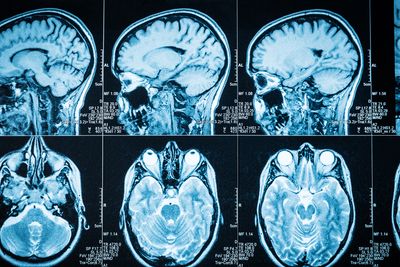

MRI (Magnetic Resonance Imaging) is a safe, non-invasive diagnostic technique that uses powerful magnetic fields and radiofrequency waves to generate detailed cross-sectional images of internal organs, soft tissues, the brain, spine, joints, and blood vessels — without any radiation exposure.

- The images are viewed in multiple planes (sagittal, coronal, axial) for better diagnosis.

- Brain MRI – Stroke, tumor, epilepsy, dementia, MS, infections